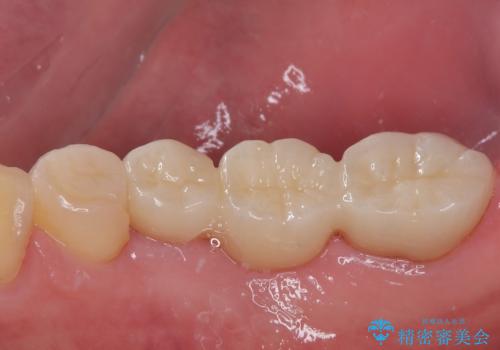

詰め物が割れた フルジルコニアクラウン

- 左下の4番目のセラミックの詰め物(セラミックインレー)が欠けたとのことで来院された患者様です。以前にセラミックの詰め物の治療を行い、噛み合わせが強く割れてしまっていました。今回はセラミックの詰め物のやり替えだとまた欠けてしまう可能性があるのでフルジルコニアクラウンでの治療を行うことにしました。拡大鏡視野下でセラミックの詰め物、虫歯を除去しフルジルコニアクラウンに適した形に整えました。

歯と歯茎の間に圧排糸と呼ばれる糸を入れてシリコーン印象を行いました。

見た目、機能面ともに満足していただけました。

噛み合わせが強い方なので今後はセラミックが割れないようにナイトガードを使っていただきながら、定期的にクリーニングで通ってもらう予定です。